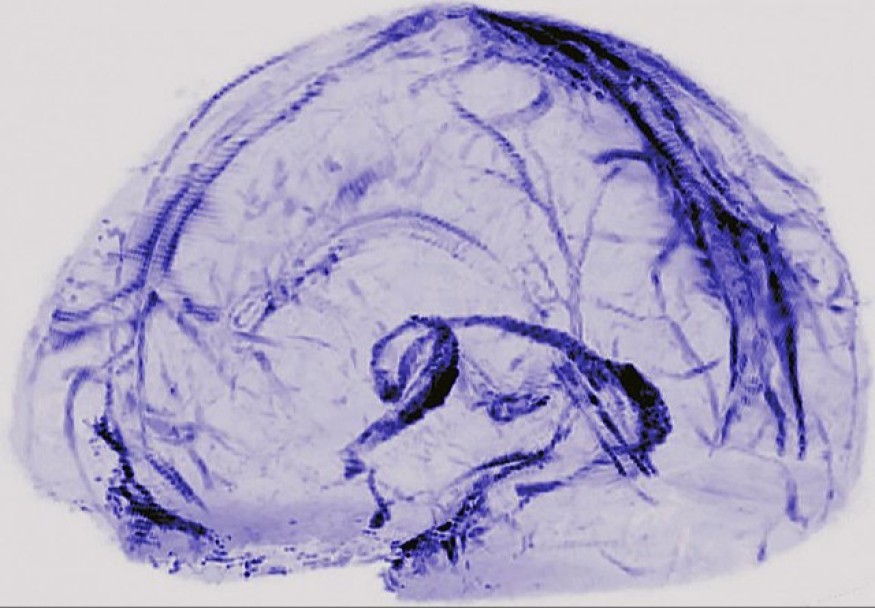

• Est-ce que le SARS-CoV2 persiste dans le cerveau ?